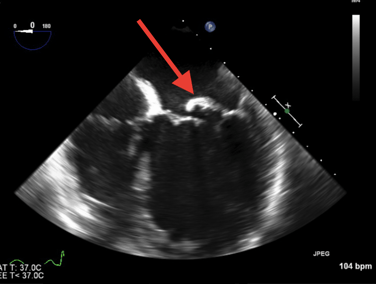

- Ecocardiograma: El ecocardiograma es una herramienta fundamental para el diagnóstico de la endocarditis. Puede ser de dos tipos:

- Ecocardiograma transtorácico (ETT): Utiliza ondas de sonido para crear imágenes del corazón desde el exterior del cuerpo, es un ultrasonido del corazón. Puede mostrar vegetaciones (acumulaciones de bacterias y tejido) en las válvulas cardíacas.

- Ecocardiograma transesofágico (ETE): Se realiza introduciendo una sonda a través del esófago para obtener imágenes más detalladas del corazón. Es especialmente útil para detectar vegetaciones pequeñas en las válvulas cardíacas.

- Evidencia de endocarditis en ecocardiograma:

- Vegetaciones detectadas en el ecocardiograma transtorácico o transesofágico, o abscesos intracardíacos.